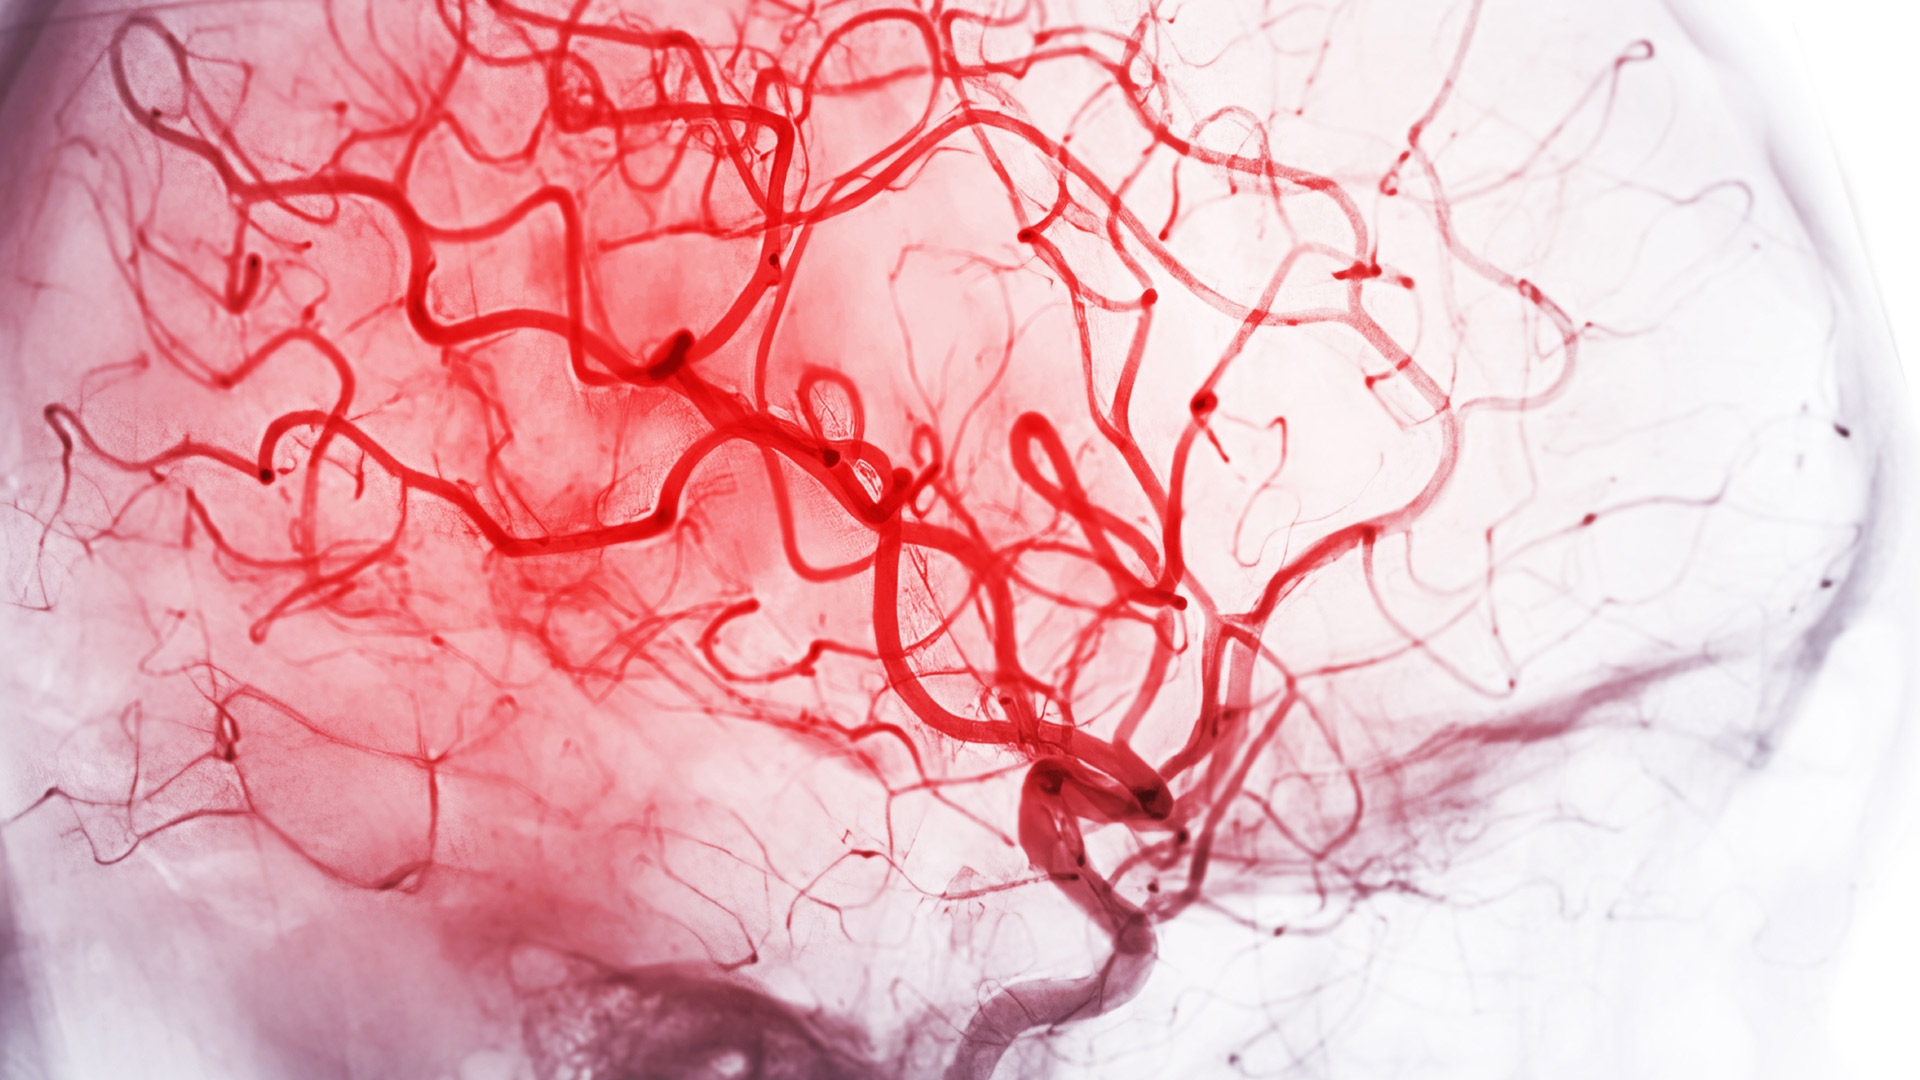

There is a growing recognition of the involvement of blood vessels in the development of dementia, with evidence now showing vascular leak as one of the earliest and most consistent vascular changes in Alzheimer disease – where the blood-brain barrier becomes compromised. This allows toxic substances to enter the brain and inhibits clearance of toxic material from the brain, triggering inflammation, amyloid accumulation, and neurodegeneration. These amyloids are abnormal protein deposits, which pack together, forming hard, sticky plaques that disrupt cell function, causing neuronal cell death and progressive cognitive decline.

Vascular leak is also a complication of anti-amyloid treatment and is a feature of the small vessel disease, cerebral amyloid angiopathy (CAA) – a major contributor to dementia of the elderly.

The drug uses new molecular glue technology to stabilise VE-cadherin, a novel target and a key protein that is essential for maintaining the blood-brain barrier integrity. The therapy aims to mend and inhibit leaky blood vessels in the brain, restore healthy vessel function and enhance clearance of toxic amyloid deposits from the brain.